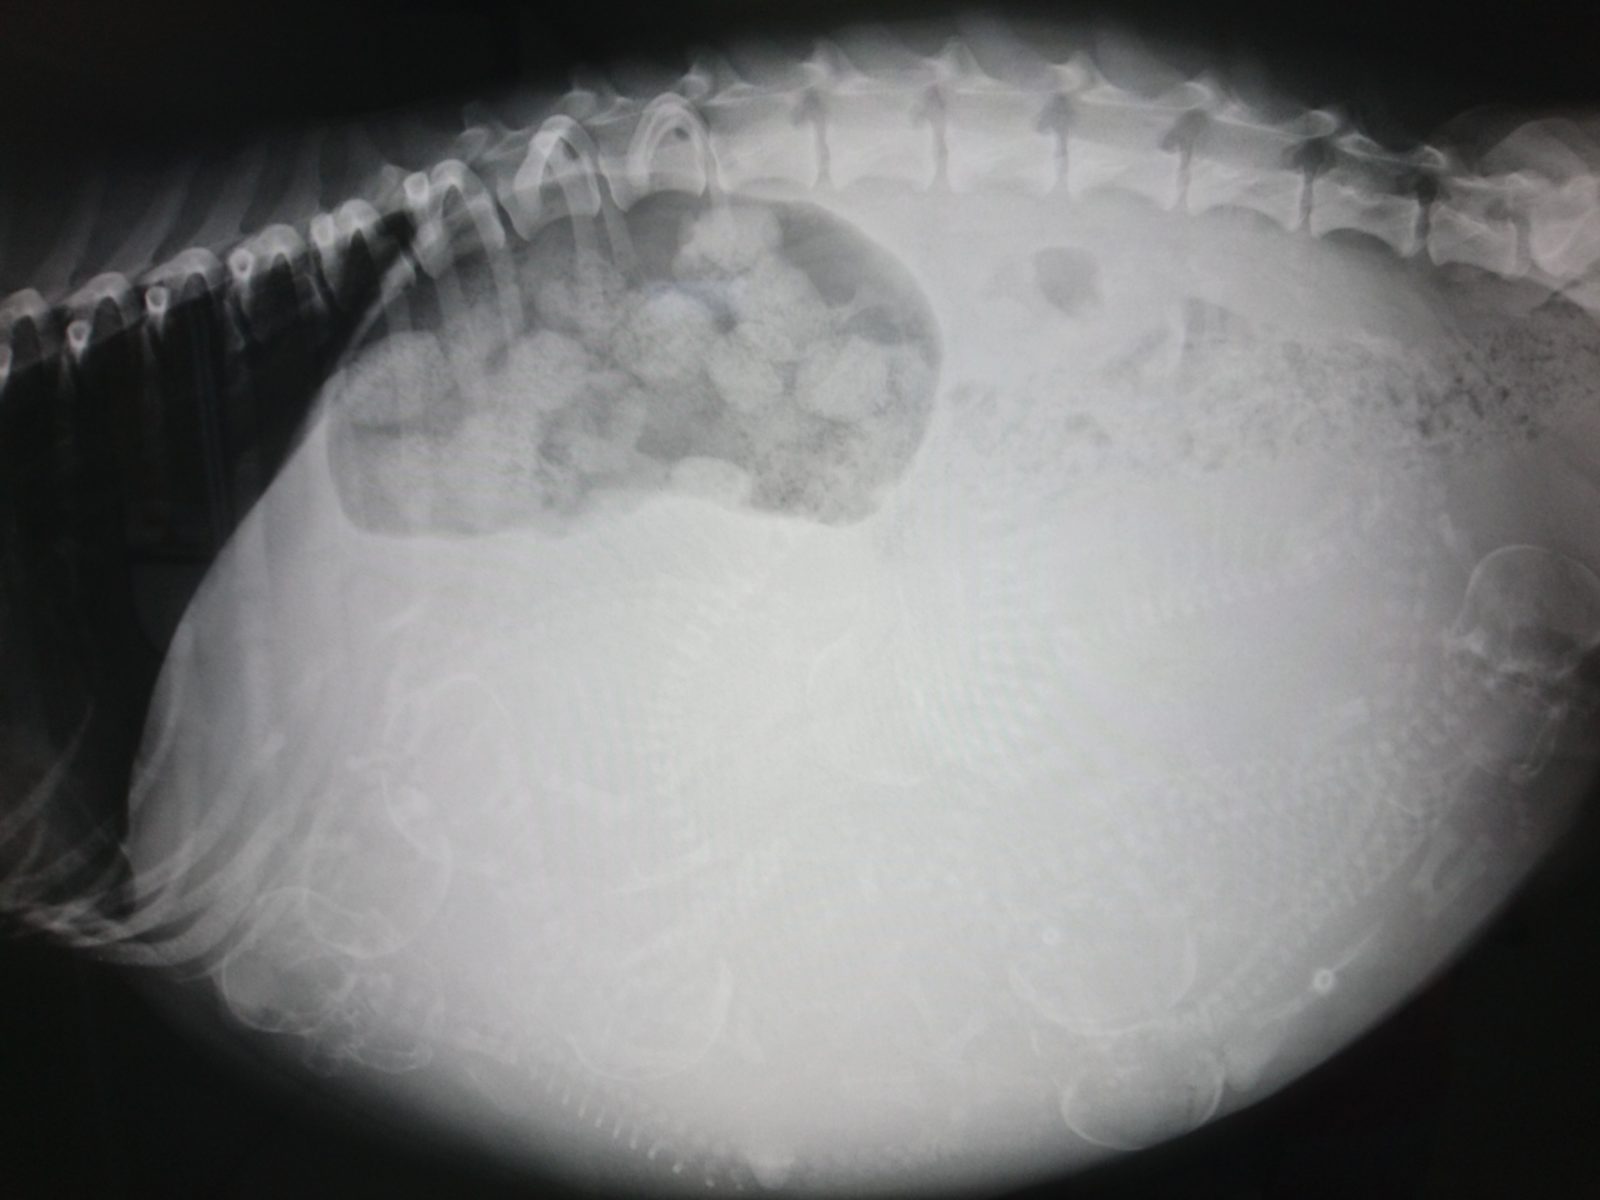

胎子ミイラ変性(たいじみいらへんせい、英: mummification of fetus)とは子宮内で死亡した胎子が無菌的に水分を失って萎縮硬化し、チョコレート色を呈する状態であり、ウシに多く発生する。胎子ミイラ変性を呈する胎子をミイラ変性胎子と呼ぶ。原因には遺伝、感染、中毒などがある。母体は黄体遺残のため無発情となる。直腸検査では子宮の膨満、胎水、波動感、子宮動脈の脈動が認められず、子宮内に弾力性のない硬い物体が認められる。ミイラ変性胎子の体表に石灰が沈着して硬化したものを石子、胎膜の表面に石灰が沈着したものを石胞と呼ぶ。ウシにおいての処置はエストリオール製剤、PGF2α製剤またはデキサメサゾンの併用注射を行う。